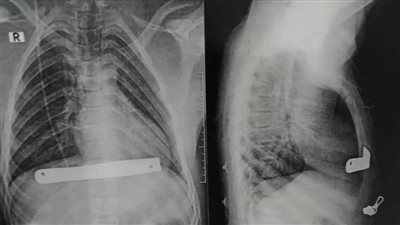

استقر بالرئة.. إنقاذ فتاة ابتلعت دبوس طرحة بمستشفى بنها الجامعي| صور

الثلاثاء 28/03/2023 03:01 م